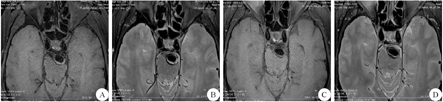

本例患者符合后循环脑梗死特点,结合影像学检查考虑VBD。入院第1天予氯吡格雷75 mg、1次/d(首次剂量300 mg),抗血小板,阿托伐他汀40 mg、每晚1次,调脂固斑,以及补液、护胃等对症治疗。入院第6天患者症状加重,出现嗜睡、中-重度构音障碍,左侧肢体肌力3-级,吞咽功能4级,复查头颅MRI提示桥脑延髓急性脑梗死,病灶范围较前增大,头颅HRMRI提示基底动脉延长扩张,伴起始段瘤样扩张,内径约9 mm,血管壁上可见小片状稍长T1长T2信号(图2A、2B),考虑基底动脉附壁血栓形成,入院第7天起改用依诺肝素钠(0.4 mL、1次/d)抗凝治疗,入院第9天患者意识转清,入院第12天球麻痹症状及左侧肢体肌力明显改善,复查头颅HRMRI示基底动脉管壁小片状稍长T1长T2信号,较前减少(图2C、2D)。出院后给予利伐沙班10 mg/d抗凝治疗,电话随访患者表示症状逐步改善,未再发脑卒中。

A:抗凝治疗前HRMRI T1上基底动脉管腔内稍长T1信号;B:抗凝治疗前HRMRI T2上基底动脉管腔内长T2信号;C:抗凝治疗后HRMRI T1上基底动脉内稍长T1信号较前减少;D:抗凝治疗后HRMRI T2上基底动脉管腔内长T2信号较前减少;HRMRI:高分辨率MRI